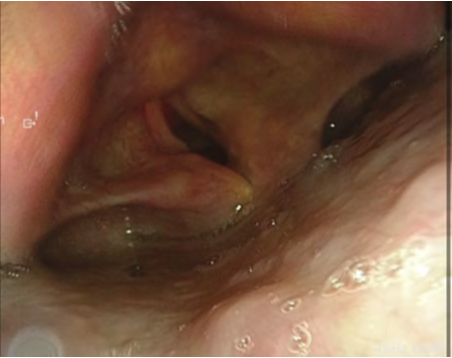

Case 2: Hypopharyngeal High-Grade Dysplasia

Following observation of the hypopharynx using the modified Killian m ethod, slight erythema was noted on the mucosa of the right pyriform sinus. NBI observation revealed a clearly demarcated brownish area with atypical microvascular proliferation at the same site. Compared with VISERA ELITE OTV-S190, VISERA S OTV-S500 provided stronger contrast and improved lesion visibility.

White Light Image

Video System Center: VISERA ELITE OTV-S190

Video Rhinolaryngoscope: ENF-VH

NBI Image

Video System Center: VISERA S OTV-S500